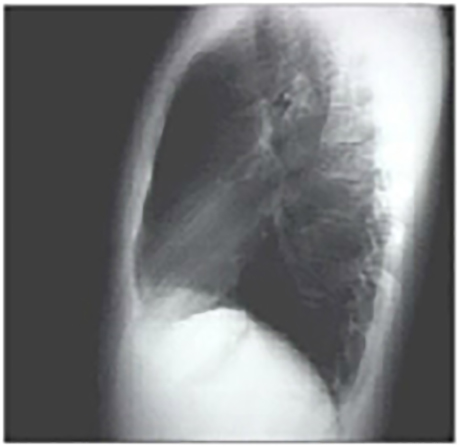

PA and Lateral

Click on the Xrays to enlarge them.

Choose the best interpretation of the chest X rays:

Entirely normal